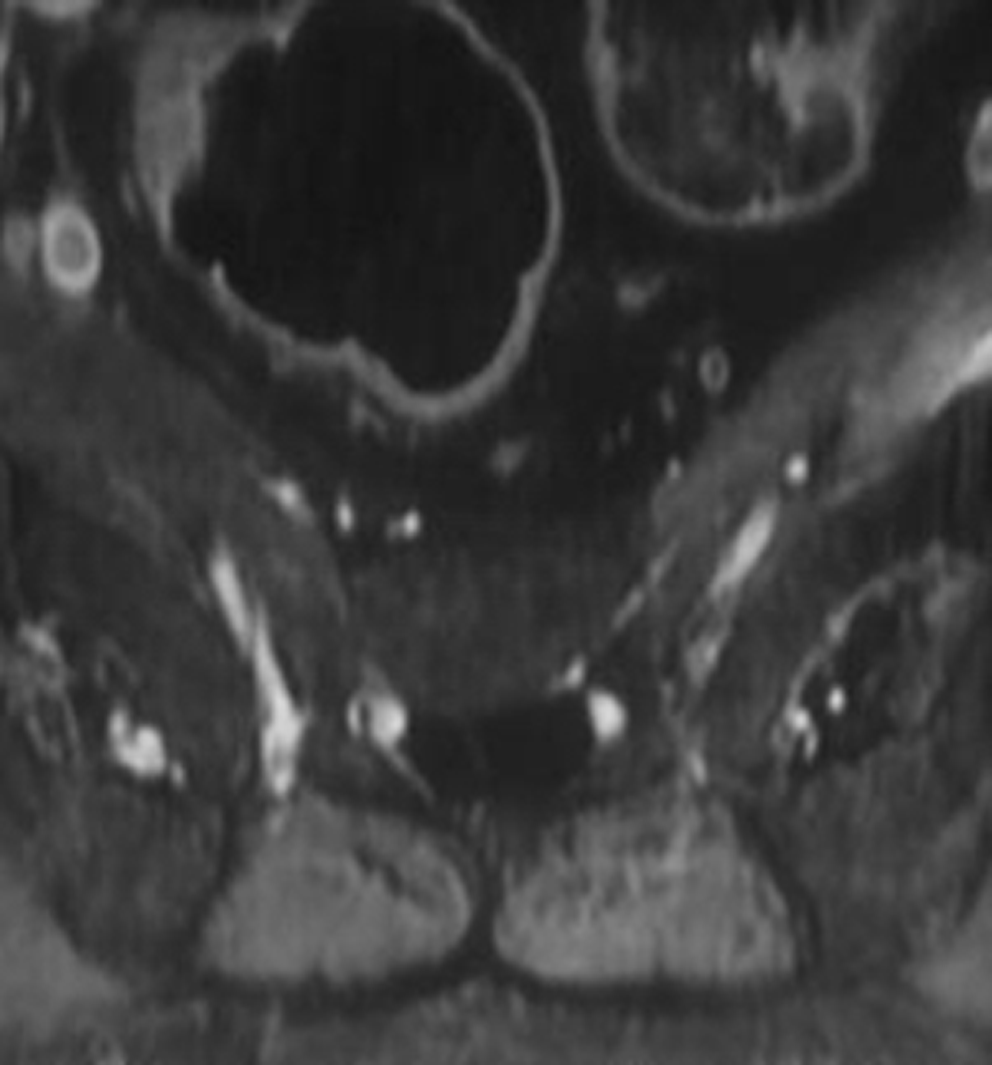

Results: All cystic lesions showed hypointense signal intensity on T1WI and hyperintense signal intensity on T2WI, but the nerve root showed iso-intensity on T1WI and low signal intensity on T2WI. They were linear in shape on sagittal view, and hypo intense dotted spots within the cysts on traverse view. Surrounding structures of the larger cysts were compressed and had bone erosions in some cases; the spinal canal and the intervertebral foramen on the affected side were enlarged. The lesions/cyst wall showed no enhancement after gadolinium administration.